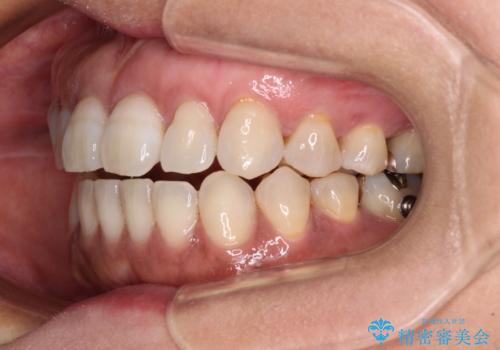

極端な上下前歯の開咬を改善 オープンバイトのインビザライン矯正

治療前に、いくらインビザライン矯正がオープンバイトを得意としているとは言え、さすがに限界があるだろうと思っておりましたが、前歯でレタスが噛めるまで改善することができました。

顔の印象も大きく変わり、患者様には大変満足していただきました。